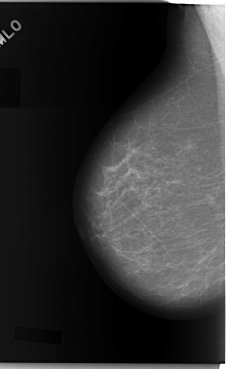

C_0081_1.RIGHT_MLO

RIGHT_MLO LINES 5896 PIXELS_PER_LINE 3616 BITS_PER_PIXEL 12 RESOLUTION 50 NON_OVERLAY